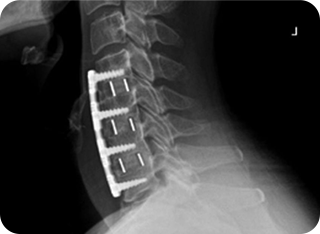

증상과 상태에 따라 개방적인 수술이 필요하며,

절개 수술을 하게 된다 하더라도 최대한

정상 디스크나 정상 뼈조직을 보존하는 수술법 적용

• 1 현미경 감압술

• 2 현미경 유합술

3단계

복합적인 치료가 필요한 경우

일반 개방형 수술

정상 조직을 최대한 보존하는 최소침습 수술!

1단계 비수술 치료와 2단계 최소침습 수술로도 증상이 호전되지 않고, 복합적인 치료가 필요한 경우에는 3단계 일반 개방형 수술(관혈적 수술)을 고려합니다.

이때 본바움병원은 환자의 부담을 최소화하기 위해 정상 디스크와 정상 뼈 조직을 최대한 보존하는 최소침습 무수혈 척추수술을 먼저 검토합니다.

이는 출혈을 줄이고 회복을 빠르게 하며, 합병증 위험을 낮추는 치료 방식으로 환자에게 최선의 결과를 제공하는 것을 목표로 합니다.